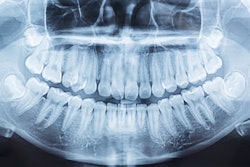

To explore the connection between poor oral health parameters and the severity of COVID-19, Donders and colleagues conducted a retrospective cohort study reviewing extraoral x-rays from 133 patients with confirmed COVID-19 to analyze alveolar bone loss and tooth loss. Patients included in the study had dental x-rays taken within a period of five years.

The analyses revealed a profound link between COVID-19 severity and alveolar bone loss and tooth loss. The odds of being admitted to an intensive care unit or dying were 5.6 times higher for patients with alveolar bone loss.

For each lost tooth, patients had 4.2% increased odds of developing severe COVID-19 versus a mild outcome. Additionally, per lost tooth, patients had 6% greater odds of developing severe versus moderate COVID-19.